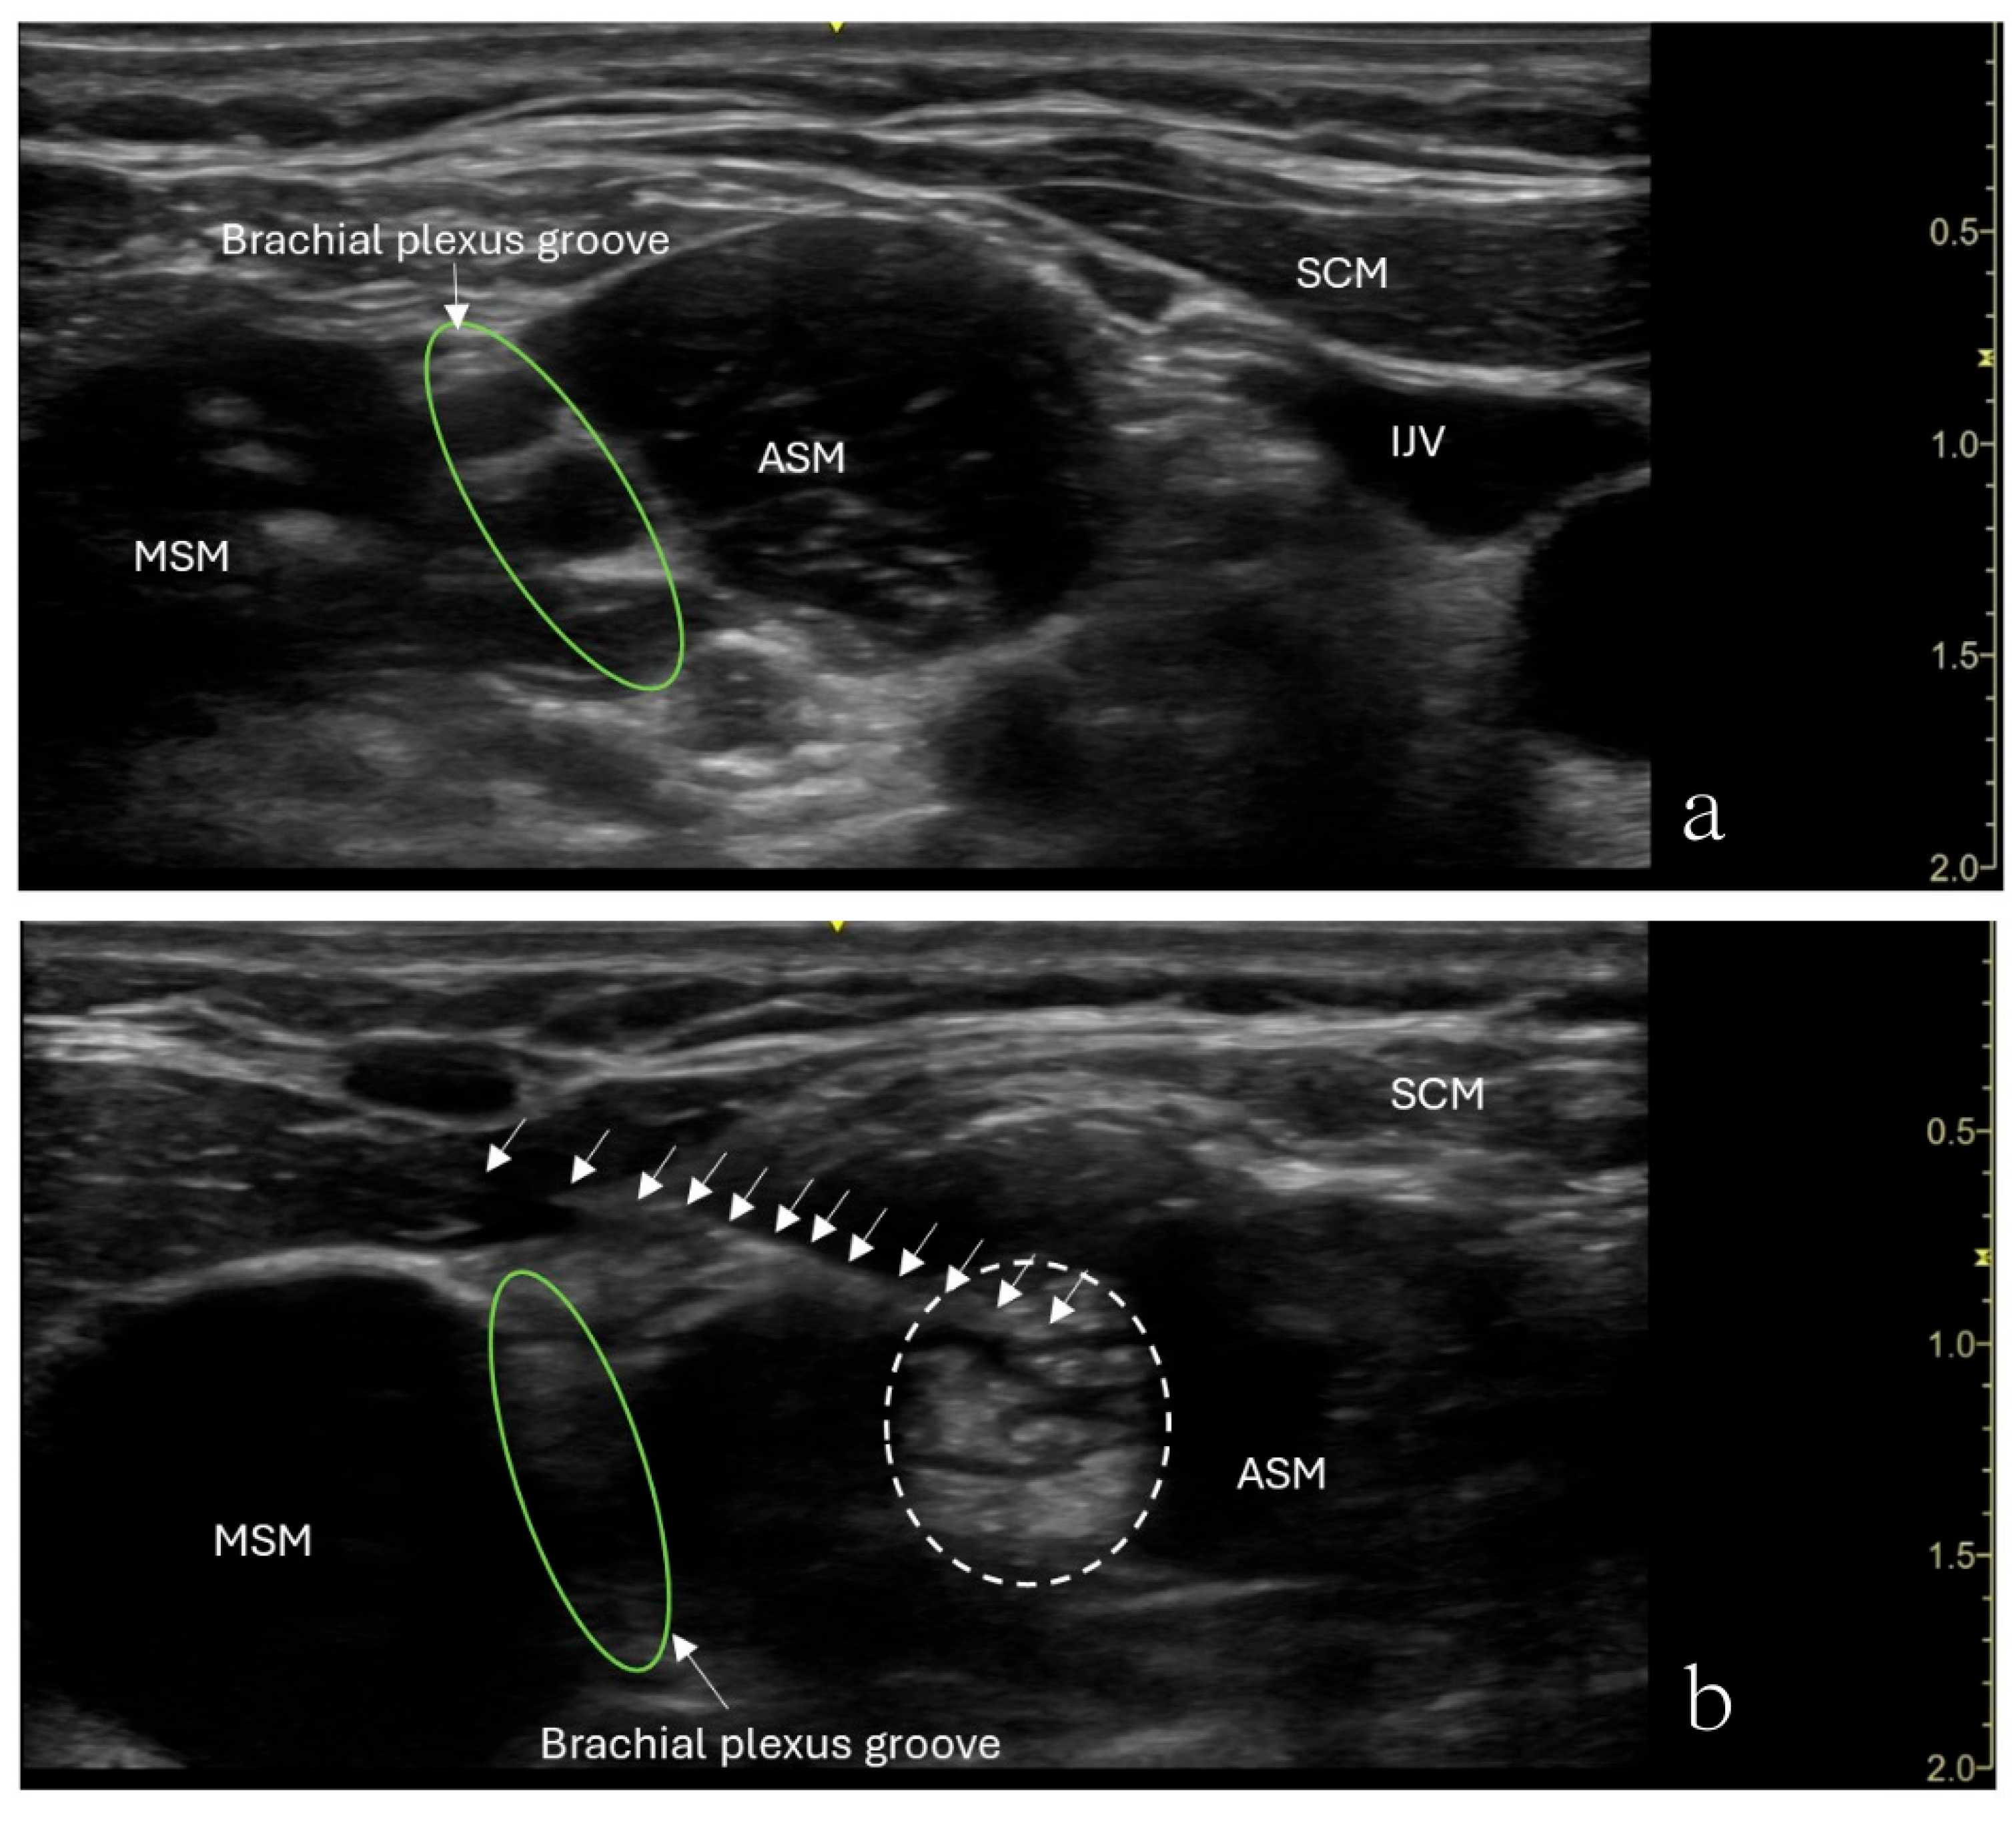

The patient underwent ultrasound-guided ASMB under minimal sedation. A high-frequency linear ultrasound probe was used to identify the anterior scalene muscle and adjacent neurovascular structures. After sterile preparation, a 24-gauge, 40 mm Sono-TAP needle (PAJUNK®, Geisingen, Baden-Württemberg, Germany), using an in-plane approach, was advanced from the anterior aspect of the neck posteriorly and inserted into the middle of the anterior scalene muscle (Figure 2). After negative aspiration, 5 mL of 0.5% ropivacaine was injected incrementally (Figure 2). The block provided immediate pain relief, and there was no numbness in the right upper extremity when the arm was elevated or abducted. However, the patient developed right-sided Horner’s syndrome and experienced weakness in the right shoulder, both of which were resolved shortly after the procedure. Her preexisting symptoms were resolved for approximately 3 h following the block.

Figure 2.

Ultrasound image showing an anterior scalene muscle block in a 15-year-old girl. (a) Needle (arrows) inserted into the anterior scalene muscle (ASM), with the needle tip placed in the middle of the anterior scalene muscle. The needle was advanced from the anterior aspect of the neck posteriorly. (b) Brachial plexus groove (green circle) is in between the ASM and MSM. Injected local anesthetics (dashed circle) and an increased muscle size were noticed.